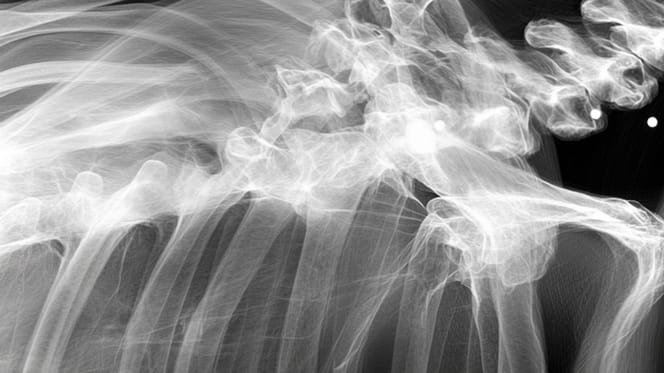

A dog's X-ray

A few years into their happy life together, Momo's owner got a nasty shock during a visit to the vet. He had taken her for a simple X-ray because she was starting to have trouble getting around. A silence fell over the consulting room as the vet explained that Momo had likely endured a very difficult and violent past. The X-ray suggested she had probably been used for mass breeding. But that wasn't all. The dog, who also suffered from arthritis and hip dysplasia, was hiding another secret.

A terrible secret

The vet soon discovered that Momo had been riddled with bullets. One of them had passed dangerously close to her spine. Fortunately, none of the bullets had a lasting impact on her life. As reported by Newsweek, this brave dog is now living the life she always dreamed of.